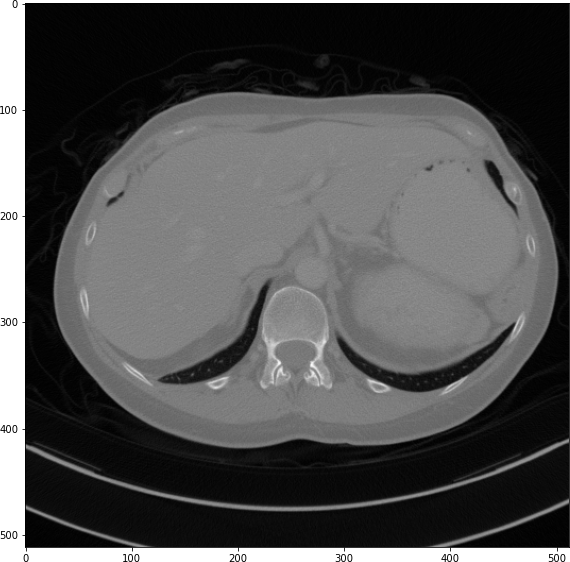

Refer to caption

(a) True Thick-slice image

(b) Simple Averaging

RMSE: 0.0357, PSNR: 34.9781

(c) Gaussian Averaging

RMSE: 0.0454, PSNR: 32.8866

(d) Direct Downsampling

RMSE: 0.0486, PSNR: 32.2861

(e) Proposed Simulation

RMSE: 0.0070, PSNR: 49.1774

Figure 4: Sagittal-plane thick-slice image quality comparison across four simulation methods.

The results from all conducted experiments, represented as mean ±plus-or-minus\pm standard deviation, are tabulated in this section. We assessed the performance of our proposed simulation method against Simple Averaging, Gaussian Averaging, and Direct Downsampling. This was accomplished by simulating images with a thickness of 3mm from those with a thickness of 1mm, utilizing the 2016 Low Dose CT Grand Challenge dataset. The results outlined in Table III provide a comparative analysis of different thick-slice simulation methods used in two datasets from the 2016 Low Dose CT Grand Challenge. Both the PSNR and the RMSE were used as key performance indicators for these methods. The data clearly demonstrate that the proposed method significantly outperformed Simple Averaging, Gaussian Averaging, and Direct Downsampling in both datasets (D45 and B30). The highest PSNR values were obtained with the proposed method, yielding 49.7369 ±plus-or-minus\pm 2.5223 and 48.5801 ±plus-or-minus\pm 7.3271 for D45 and B30 datasets, respectively. The proposed method also registered the lowest RMSE with values of 0.0068 ±plus-or-minus\pm 0.0020 and 0.0108 ±plus-or-minus\pm 0.0099 for D45 and B30, respectively. These results indicate a superior level of accuracy and reliability in the proposed method. The statistically significant differences were confirmed by a Wilcoxon signed-rank test with p-value ¡ 0.05, implying that the improvements from the proposed method were not due to random chance. These findings support our first hypothesis that the proposed simulation method provides a more efficient and precise approach to thick-slice simulations compared to traditional methods. To provide a more comprehensive evaluation, visual comparisons from axial, coronal and sagittal plane were also undertaken, as depicted in Figures 2 to 4. In summary, Our proposed method demonstrated substantial enhancements in terms of both PSNR and RMSE, indicating a distribution more closely aligned with the authentic thick-slice image.